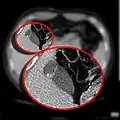

In medicine, a Phrygian cap is the folded portion of some gallbladders that resembles the Phrygian cap (a soft conical cap with the top pulled forward, associated in antiquity with the inhabitants of Phrygia, a region of central Anatolia). It is a normal anatomical variant seen in 1-6% of patients.[1] It is caused by a fold in the gallbladder where the gallbladder fundus joins the gallbladder body.[2] Apart from the chance of being mistaken for stones on a sonogram, it has no other medical implications nor does it predispose one to other diseases. However, due to potential decrease in bile flow, it may warrant a preventive removal of the gallbladder.

- CT scan showing a phrygian cap